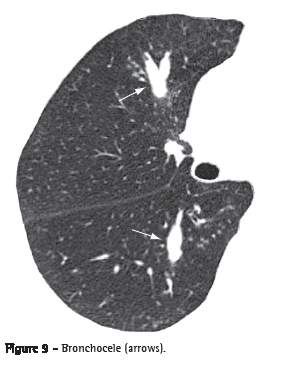

Bronchocele (broncocele)

Bronchocele is characterized by bronchial dilation with secretion accumulation (mucoid impaction), generally caused by proximal obstruction, which might be congenital (e.g., bronchial atresia) or acquired (e.g., allergic bronchial aspergillosis).(21) Bronchocele is observed as a

tubular or branched image that resembles the finger of a glove (Figure 9).

In cases of bronchial atresia, decreased attenuation of the lung

parenchyma distal to the lesion can be observed on CT scans.